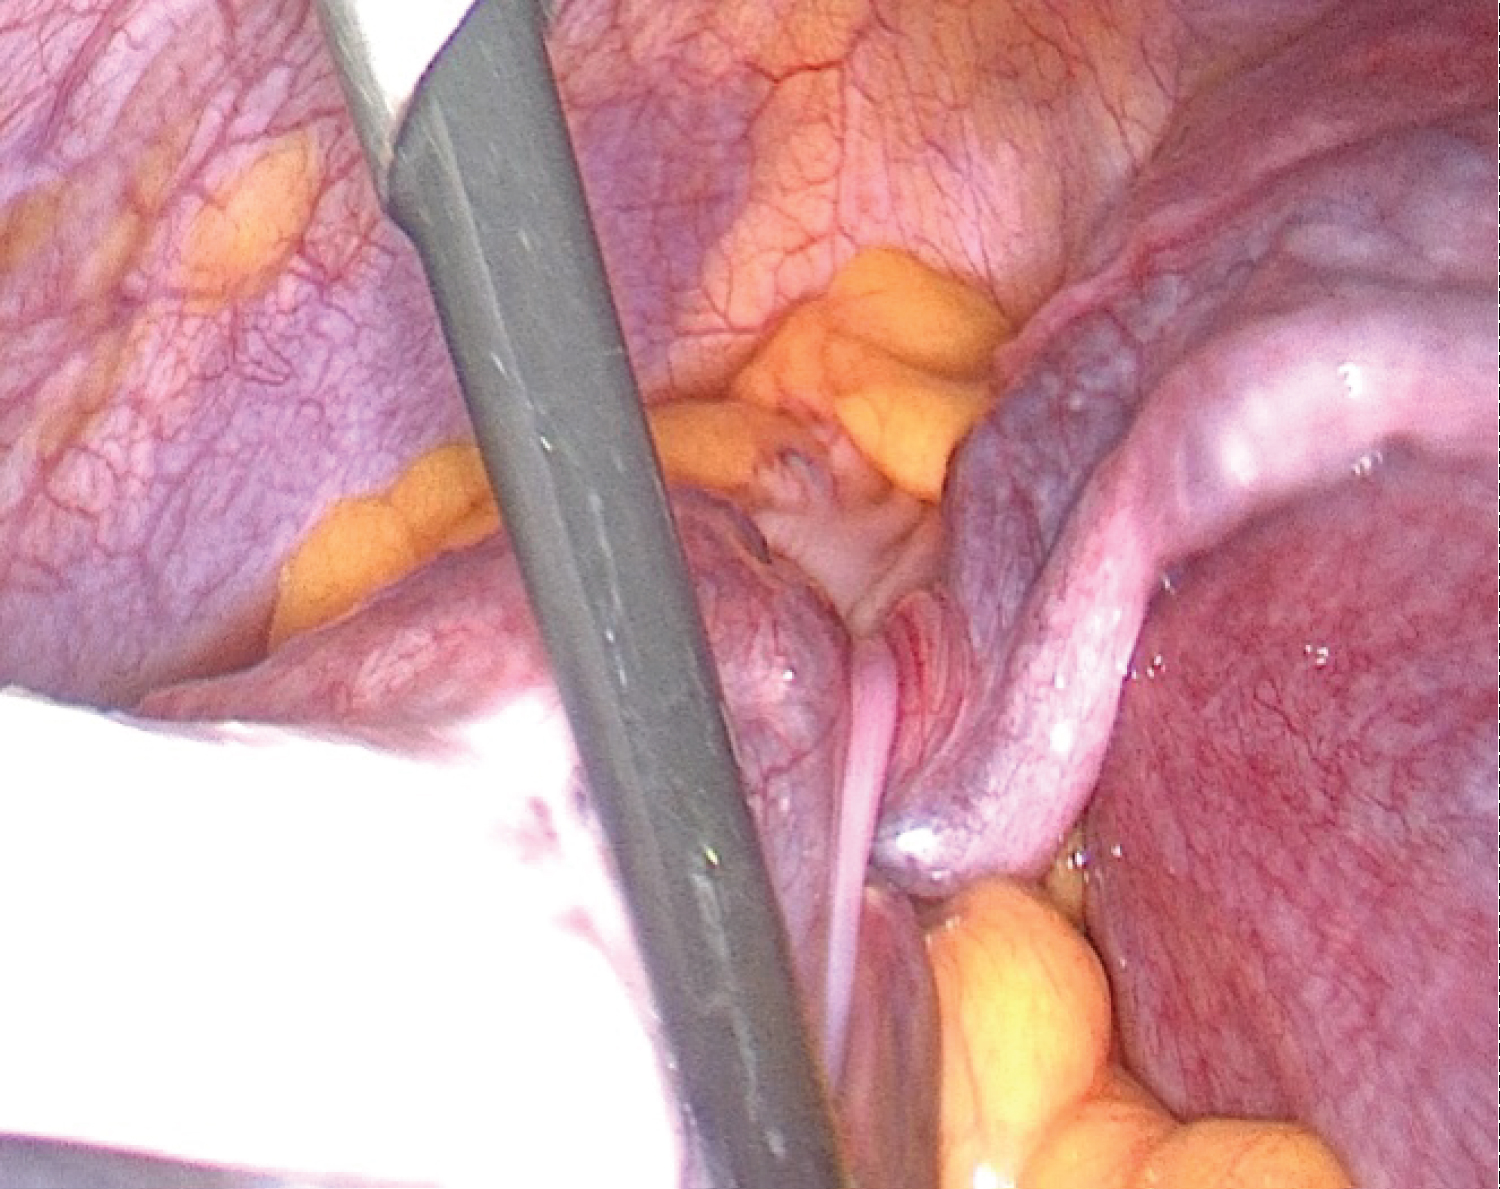

When we were faced with a patient who was in severe pain, we decided to perform a diagnostic laparoscopy. Exploration revealed a large functional cyst measuring 15 * 10 cm (Figure 1). The fallopian tube was twisted with three turns of the spiral (Figure 2) and an epiploic appendigitis (Figure 3). After evacuation of the cyst, a detorsion was performed. Yellow fluid was obtained, confirming the functional origin of the cyst, followed by resection of the epiploic appendigitis. Postoperative follow-up was favorable and the patient was discharged one day later. The ultrasound after 2 weeks showed an evolving pregnancy.

Figure 2: The twisted fallopian tube. View Figure 2